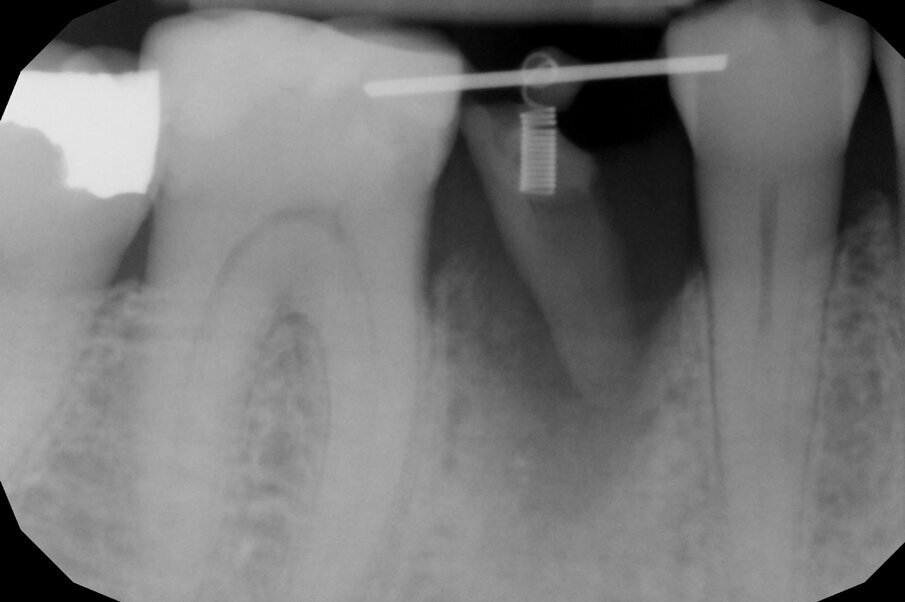

In questo caso clinico la difficoltà consisteva nel fatto che si è resa necessaria l’estrazione della metà mesiale della radice fratturata e quindi nel far compiere al frammento radicolare rimasto un movimento diagonale per mezzo del quale la porzione distale rimasta con il legamento parodontale avrebbe permesso una corretta rigenerazione tissutale ossea come indicato in rosso nell’immagine radiografica.

Per ottenere questo risultato nel gennaio 2021 è stato ancorato un segmento di arco in acciaio a sezione quadrata 0.021” x 0.025” agli elementi 4.4 e 4.6 per mezzo di composito. Il segmento è servito da ancoraggio per una molla con forza di trazione 150 g in posizione obliqua in senso disto-mesiale.

L’estrusione completa del frammento ha richiesto un tempo di 6 mesi, durante i quali è stata modificata più volte l’inclinazione della molla per evitare che il movimento diventasse ortogonale al segmento e mantenere la traiettoria prevista. Così facendo, è stato possibile rigenerare naturalmente l’intero alveolo e inserire, dopo 3 mesi di ulteriore maturazione del tessuto, in un contesto osseo ideale e perfettamente rigenerato un impianto Syra (Sweden & Martina) di diametro 4.25 mm e lungo 11 mm.